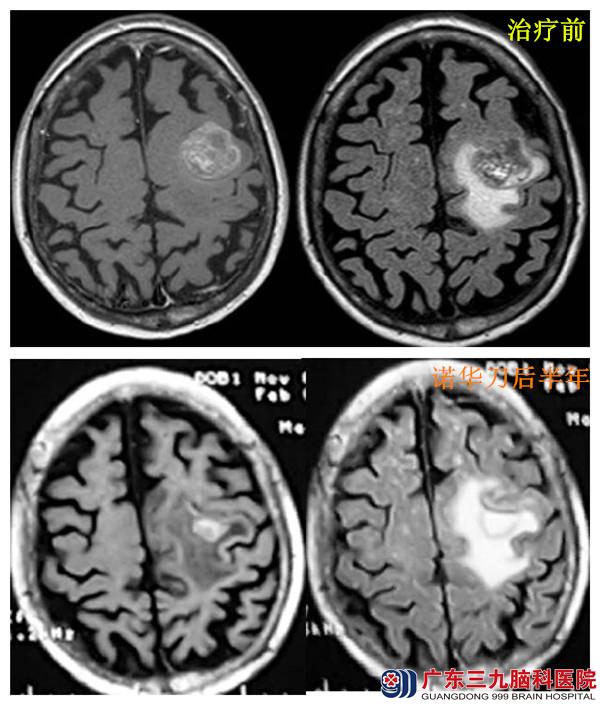

入院后完善相关检查,查体右侧肢体肌力Ⅲ级,全身PET-CT检查结果:1.左侧额叶占位,考虑转移瘤伴出血;2.左肾术后缺如,右肾萎缩,右肾下盏结石。诊断:1.左额叶占位性病变,转移瘤可能性大;2.左肾鳞状细胞癌;3.双肾多发结石;4.肾功能不全。予患者分别行两次诺华刀治疗,共三个病灶,三个等中心,过程顺利,患者无特殊不适。

患者于诺华刀治疗后半年复查:神清、对答切题、查体合作、右侧肢体肌力V-级、肌张力正常。